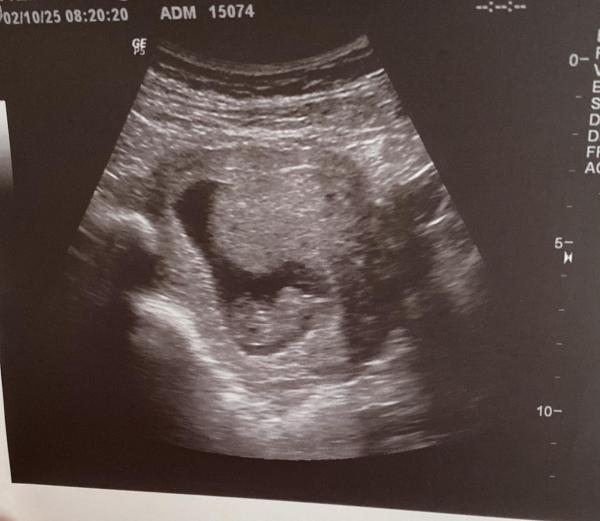

Huhu :) Ach gottchen, bei dir sieht man ja alles schon voll gut. Bei mir wurde bei 10+2 schon über die Bauchdecke geschallt. Man konnte leider nicht so gut erkennen, was was ist und ich habe es vor Aufregung auch gleich wieder vergessen, wie herum es lag. Aber wir haben es sich bewegen gesehen und das hat alles einfach nochmal viel realistischer gemacht. (Generell hängt das sicherlich vom Alter des Geräts ab...) Mein Mann hätte fast geweint vor Freude. Ich wurde übrigens auf 9+5 korrigiert, ich hänge mein Bild vom 2.10. gern mal an. Mein nächster Termin ist am 30.10.... Liebe Grüße :)